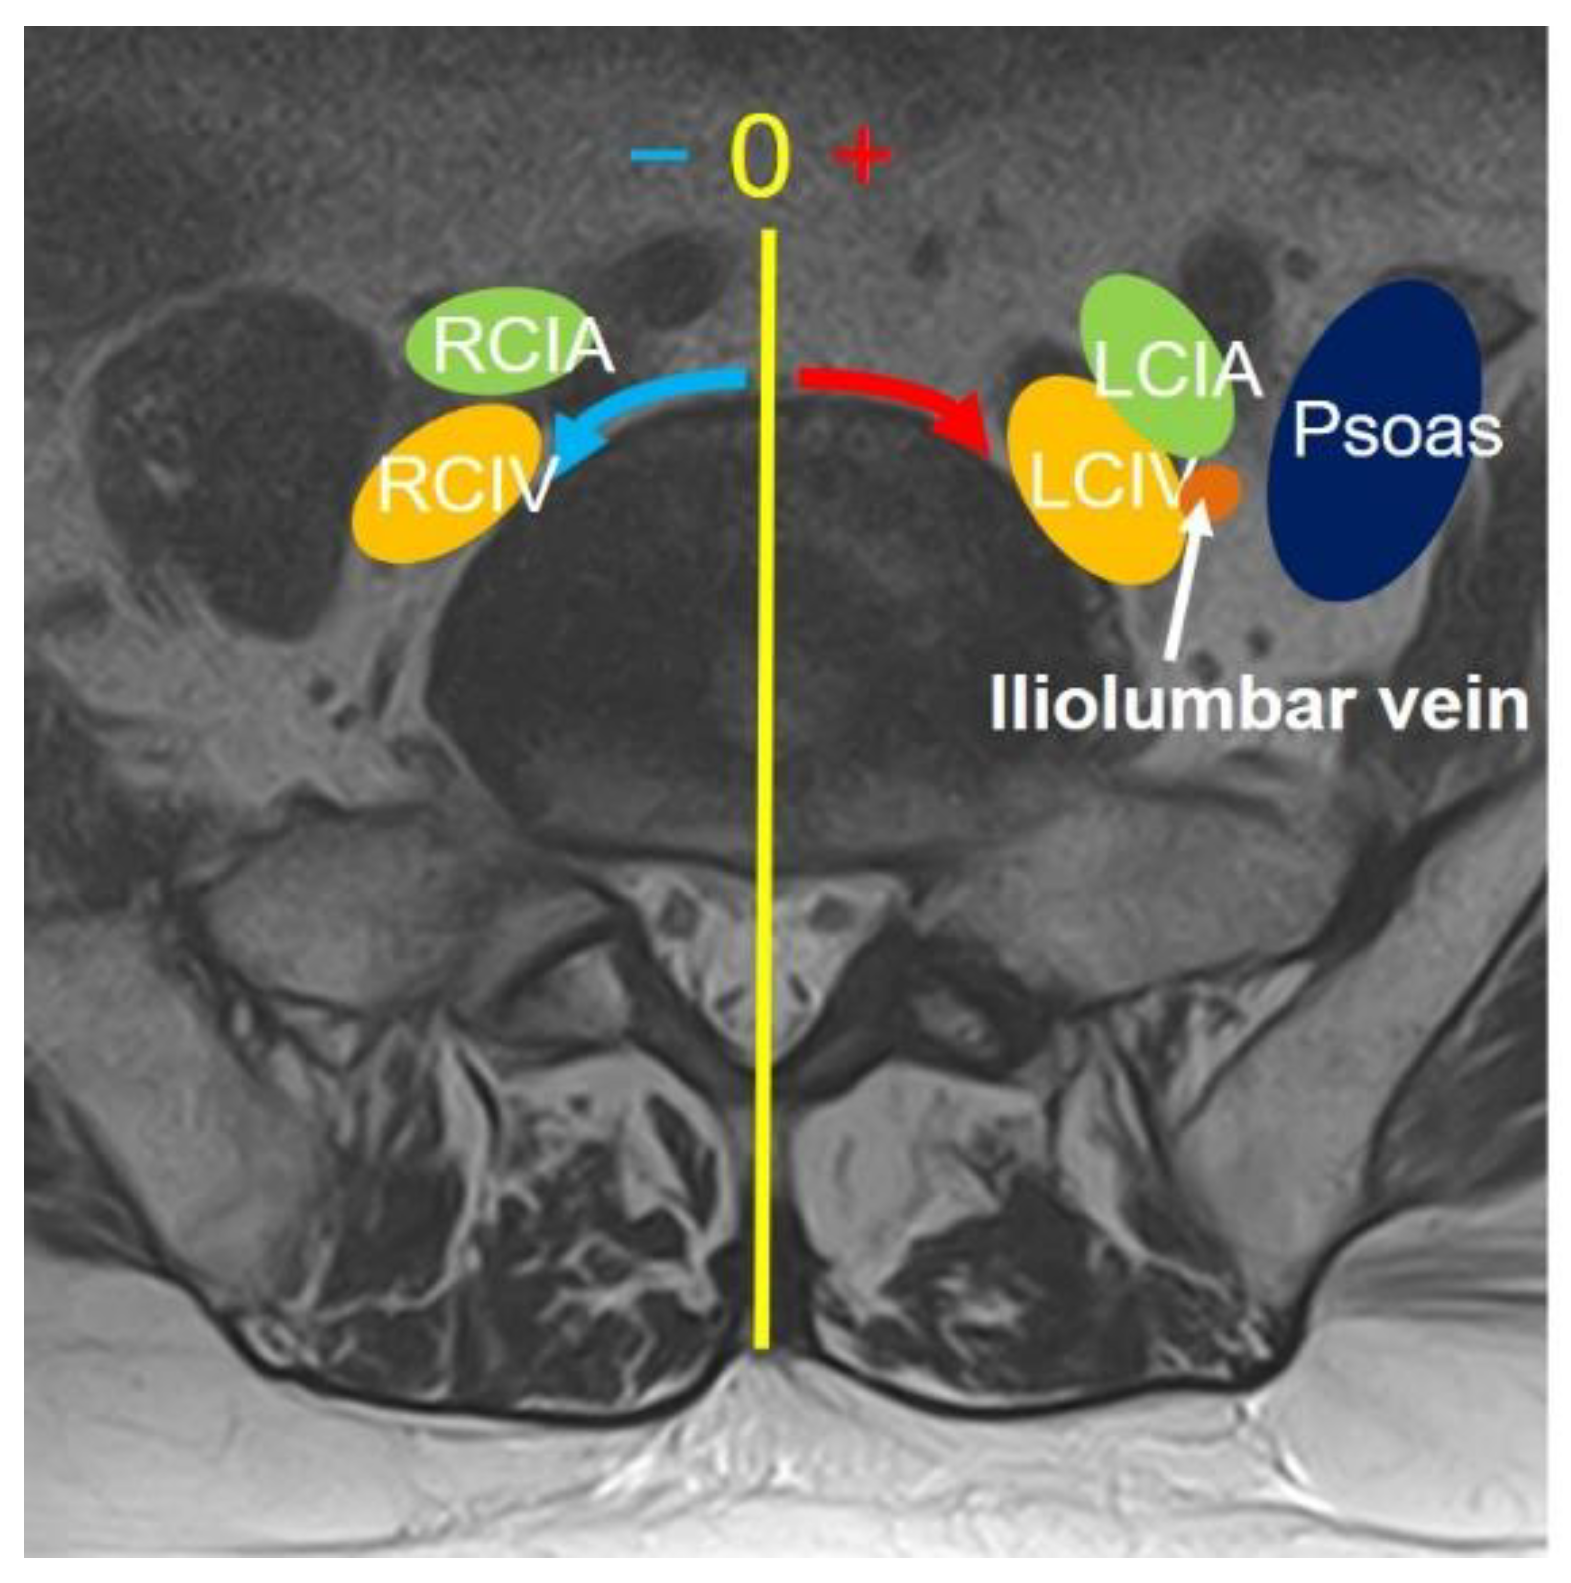

Evaluation of vascular anatomy in supine position on MRI

On MRI axial scan at either lower L5 endplate and S1 endplate level, the distance from sagittal mid-vertebral line to border of right and left common iliac vessels were measured as (L5-LCIV, L5-RCIV, L5-LCIA, L5-RCIA, S1-LCIV, S1-RCIV, S1-LCIA, S1-RCIA) (Figure 2). The vascular window was measured between right and left iliac vessels, expressed as central corridor window (CCW). The lateral corridor window was expressed as the distance between the lateral border of left common iliac vein and medial border of psoas muscle (LCW) (Figure 2). The iliolumbar vein anatomy was also evaluated in terms of visualization rate (%), axial position from sagittal mid-vertebral line (L5-ILV, S1-ILV). The type of iliolumbar vein was classified according to Nalbandian et al. (Nalbandian) (Figure 3). Type 0 refers to no ILV, Type 1 is the single variant. Multiple ILVs are categorized into type 2, 3, and 4 according to the number of veins found. The vertical position of common iliac vein bifurcation was measured from the lower endplate of L5 (Figure 4).

Figure 2. Measurement of vascular position at L5/S1 disc level. The distance from the midline of the disc to each vascular tissue was measured either counterclockwise (minus) or clockwise (plus). RCIA: right common iliac artery; RCIV: right common iliac vein; LCIA: left common iliac artery; LCIV: left common iliac vein; Psoas: Iliopsoas muscle.